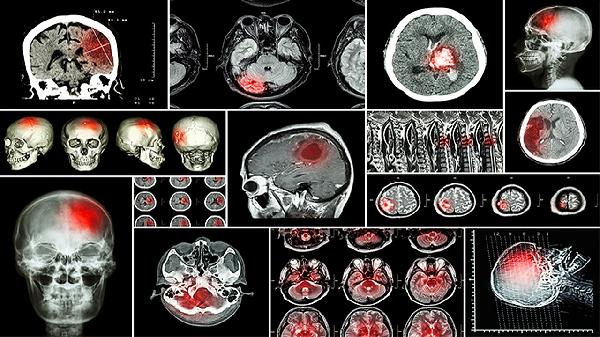

脑供血不足没有特效药,治疗需根据病因选择药物,常用药物主要有阿司匹林肠溶片、阿托伐他汀钙片、尼莫地平片、长春西汀片、盐酸氟桂利嗪胶囊等。脑供血不足可能与动脉粥样硬化、高血压、颈椎病等因素有关,需在医生指导下规范用药。